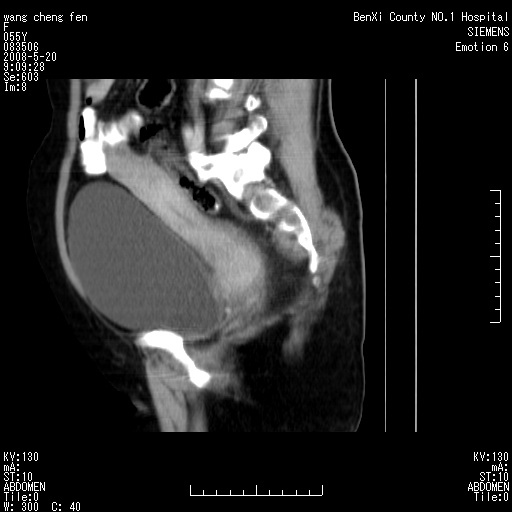

女、绝经后阴道流血3个月

左侧附件区可见一囊性占位,边缘清楚,内可见不规则形软组织影 ce:囊壁及内部可见强化 考虑 卵巢囊腺瘤

左侧附件区巨大囊实性病灶,边缘光整,病灶囊壁较厚,增强示囊壁及实性部分明显强化,强化呈度与宫体实质大致相同,宫腔积液征像,未见盆腔积液等其他异常,考虑左侧卵巢囊腺癌,不除外囊腺瘤及浆膜下肌瘤坏死

左侧附件区巨大囊实性病灶,边缘光整,病灶囊壁较厚,增强示囊壁及实性部分明显强化,强化呈度与宫体实质大致相同,宫腔积液征像,未见盆腔积液等其他异常。绝经后阴道流血3个月,结合病史左侧卵巢囊腺癌首先考虑,宫腔扩大不除外累及。期待结果。

支持浆膜下子宫肌瘤.之前由于网络原因未看全图片,现在重看,宫颈见一类圆形低密度影,增强轻度强化,低于肌层强化,宫腔扩大,考虑宫颈癌伴宫腔积液可能性大.

囊实性肿块分隔厚度较大,厚薄不均,增强实性成分明显强化,有不规则阴道流血,卵巢囊腺癌可能性大。

1,宫颈部占位,宫颈癌?2,左侧附件区囊实性占位,界较清,实质部分强化明显。考虑浆膜下或阔韧带肌瘤囊变可能大。囊腺类肿瘤不除外。